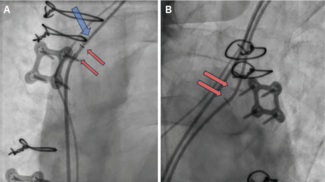

James Greelish, MD; Gregory Woo, MD, FHRS, FACC; Brittany Eaker, MSN, FNP-C; Kolade Agboola, MD, FACC; John Schindler, MD, FACC; Rick Turek, BS, CCDS

Brittany Eaker, MSN, FNP-C, et al describe their initial experience retrieving a leadless pacemaker from the pulmonary artery.

11/14/2025